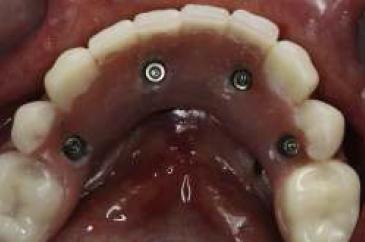

La planificación se realizó por medio de una ortopantomografía (fig. 5), evitando la utilización de cone-beam, siguiendo nuestro objetivo de realizar un tratamiento con un bajo costo. Al momento de la cirugía la paciente se encontraba premedicada con amoxicilina de 500 mg cada 8 h desde el día anterior15,16, ibuprofeno 400 mg cada 8 h10, comenzando 1 h antes de la cirugía17 y colutorios de clorhexidina al 0,12%, habiendo iniciado el tratamiento 48 h antes del procedimiento quirúrgico4. En el pabellón se probó nuevamente la guía multifuncional en boca (fig. 6), se anestesió a la paciente para luego realizar una incisión crestal desde la zona del primer molar derecho a la zona del primer molar izquierdo10,15,18, con incisiones liberadoras bilaterales, para luego realizar la disección subperióstica lingual y vestibular18. Con la plantilla radiográfica proporcionada por el fabricante se seleccionó sobre la radiografía panorámica el largo de los implantes a colocar. La cantidad de tejido óseo en sentido vestíbulo-lingual observada durante la cirugía fue de 5-6 mm, por lo que los implantes utilizados fueron implantes cónicos Strong SW de hexágono interno (SIN®, Sao Paulo, Brasil) de 3,8 mm de diámetro. Con la ayuda de la guía como referencia, se colocó 2 implantes distales, uno en cada lado, en la zona de los primeros premolares, inclinados a distal5, teniendo una longitud de 13 mm. Otros 2 implantes se colocaron a cada lado de la línea media mandibular, con una longitud de 15 mm. Se comprobó que los 4 implantes tuviesen una estabilidad primaria superior a los 30 N/cm (fig. 7). Se instalaron pilares Mini-Abutment y cilindros de protección de pilar, también teniendo como referencia la guía multifuncional. Se eligió suturar los tejidos con sutura no reabsorbible 4-018,19 (Seda, Ethicon, Johnson & Johnson, Brasil), siguiendo nuestro objetivo de disminuir los costos del procedimiento, y se envió a la paciente a la sala de recuperación (fig. 8).

Al tercer día se realizó la instalación con torque manual y ajuste oclusal (figs. 13,14,15,16).

A los 10 días, luego de la cirugía, se citó a la paciente a control para realizar la retirada de la sutura11; se dio torque a los tornillos protésicos (10 N/cm) y se chequeó la oclusión nuevamente. Se ha seguido controlando a la paciente cada 6 meses, hasta cumplir 2 años desde la fecha de instalación de la aparatología, sin manifestar complicación alguna (figs. 17, 18, 19, 20, 21).